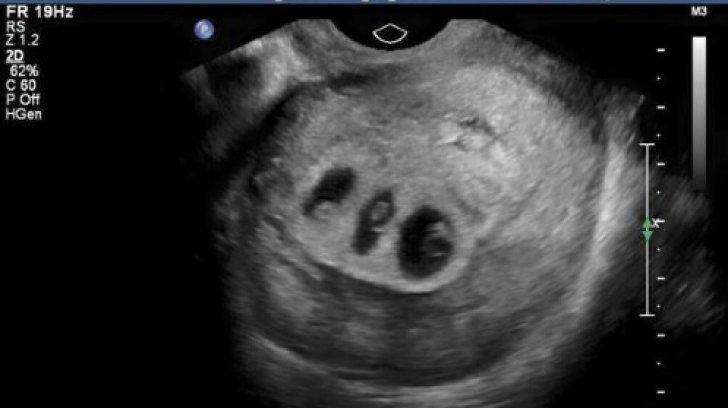

Doctorii i-au spus să aleagă care dintre cei 3 bebeluși va trăi. Decizia ei a șocat o lume întreagă!